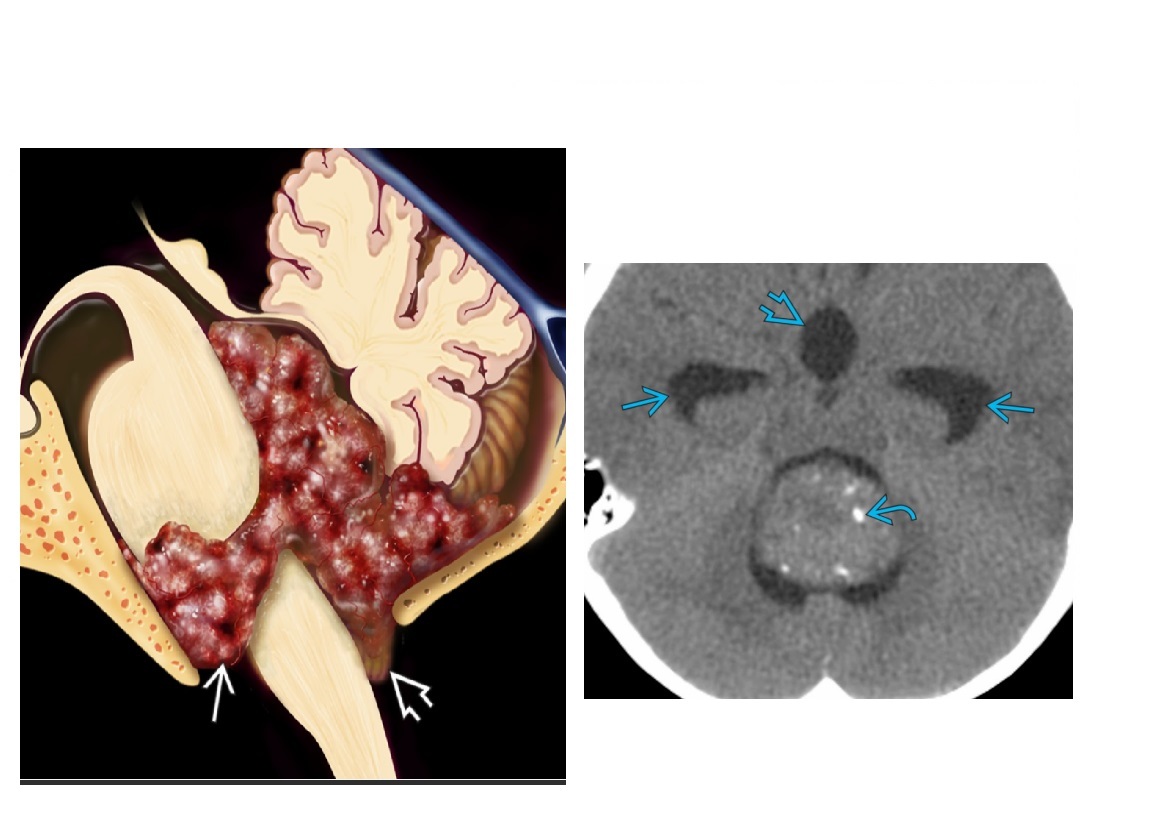

8

Q

Mass in the inferior 4th ventricle of child with hypointensity on T1 and foci of high T2 signal ?

A

Ependymoma

4th ventricle mass (± indistinct interface with floor of 4th ventricle)

Fine, stippled Ca⁺⁺ common (50%)

± cysts, hemorrhage

Hydrocephalus common

Hetergenous Signal as Ca2+/Blood products

- overall T1 iso/hypointense and T2 hyerpintense

Anterolateral extension through recess(es) into CPA cistern

Posteroinferior extension through foramen of Magendie into cisterna magna